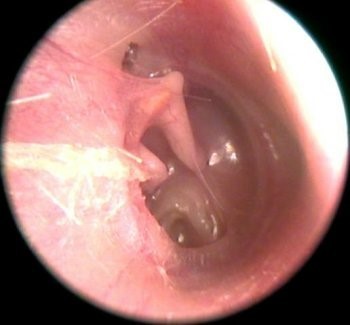

鼓膜穿孔

中耳鼓室黏膜一旦出现炎症,就会刺激渗出很多无菌或病菌性分泌物,这些分泌物会由于积液挤压或毒性作用引起鼓膜穿孔,从而导致鼓膜的振动传音功能下降,引起传导性听力下降

脓性干痂、中耳胆脂瘤的机械性堵塞,引起传导性听力下降;

中耳胆脂瘤

中耳胆脂瘤是常见的中耳炎亚型,这种中耳炎患者可以由于胆脂瘤的挤压侵袭破坏听小骨骨质,引起听小骨链断开,传导功能丧失或降低,导致传导性听力下降;